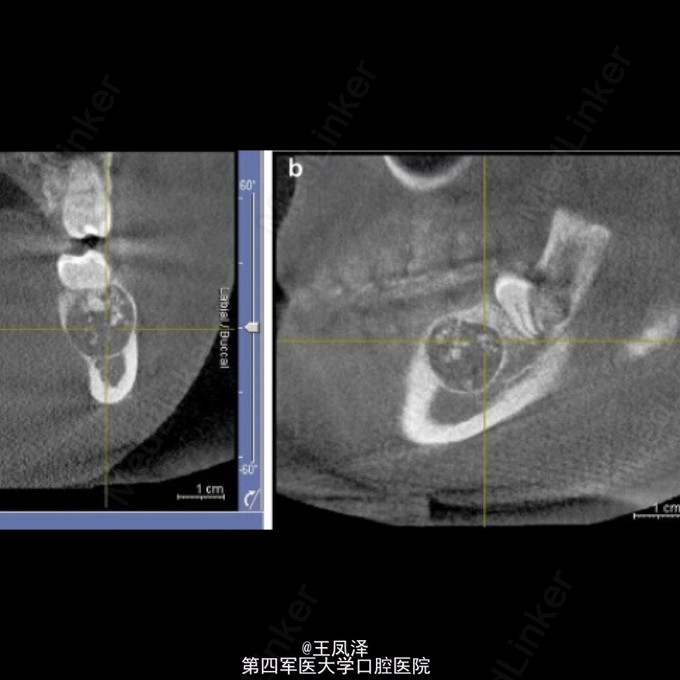

罕见左侧下颌骨牙本质生成性影细胞瘤一例

患者,女,20岁,自诉左侧下颌磨牙区疼痛不适,不能咀嚼来诊

以巨大囊肿为表现的牙本质生成性影细胞瘤